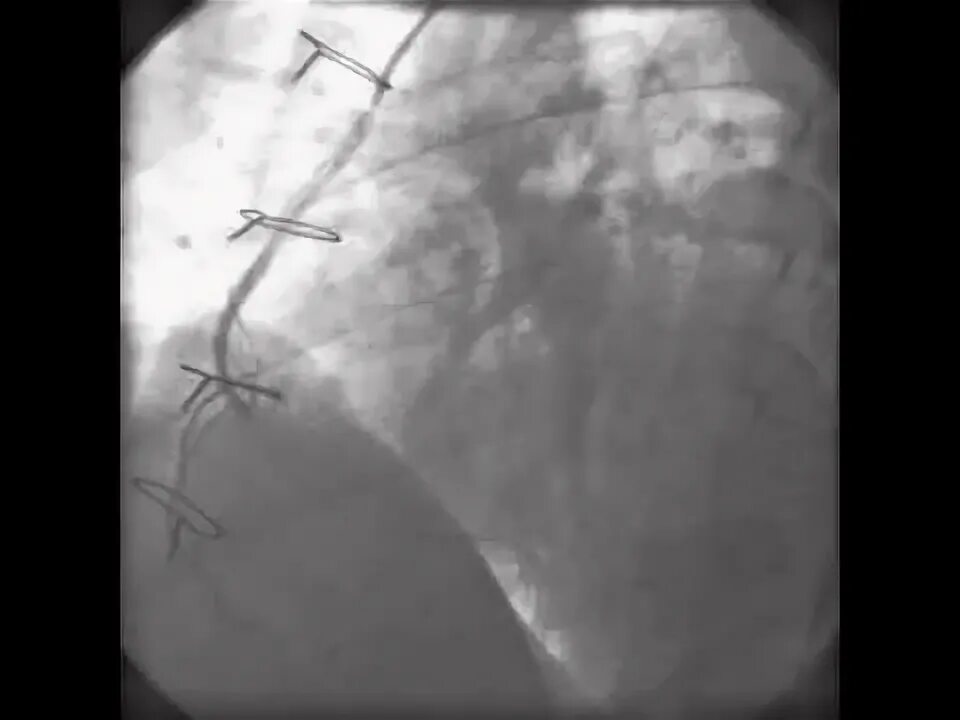

Эмболизация гемангиомы